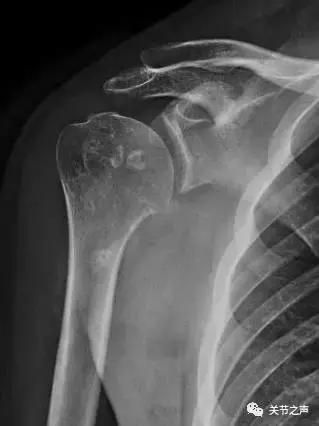

关节腔里的“珍珠”,就是我们常说的关节游离体,膝关节最多见,其次是肩关节。这种“珍珠”大多是一种良性肿瘤,叫滑膜软骨瘤病。

除了肩关节,髋、膝、踝、肘、腕几乎全身各个关节都有可能长珍珠。